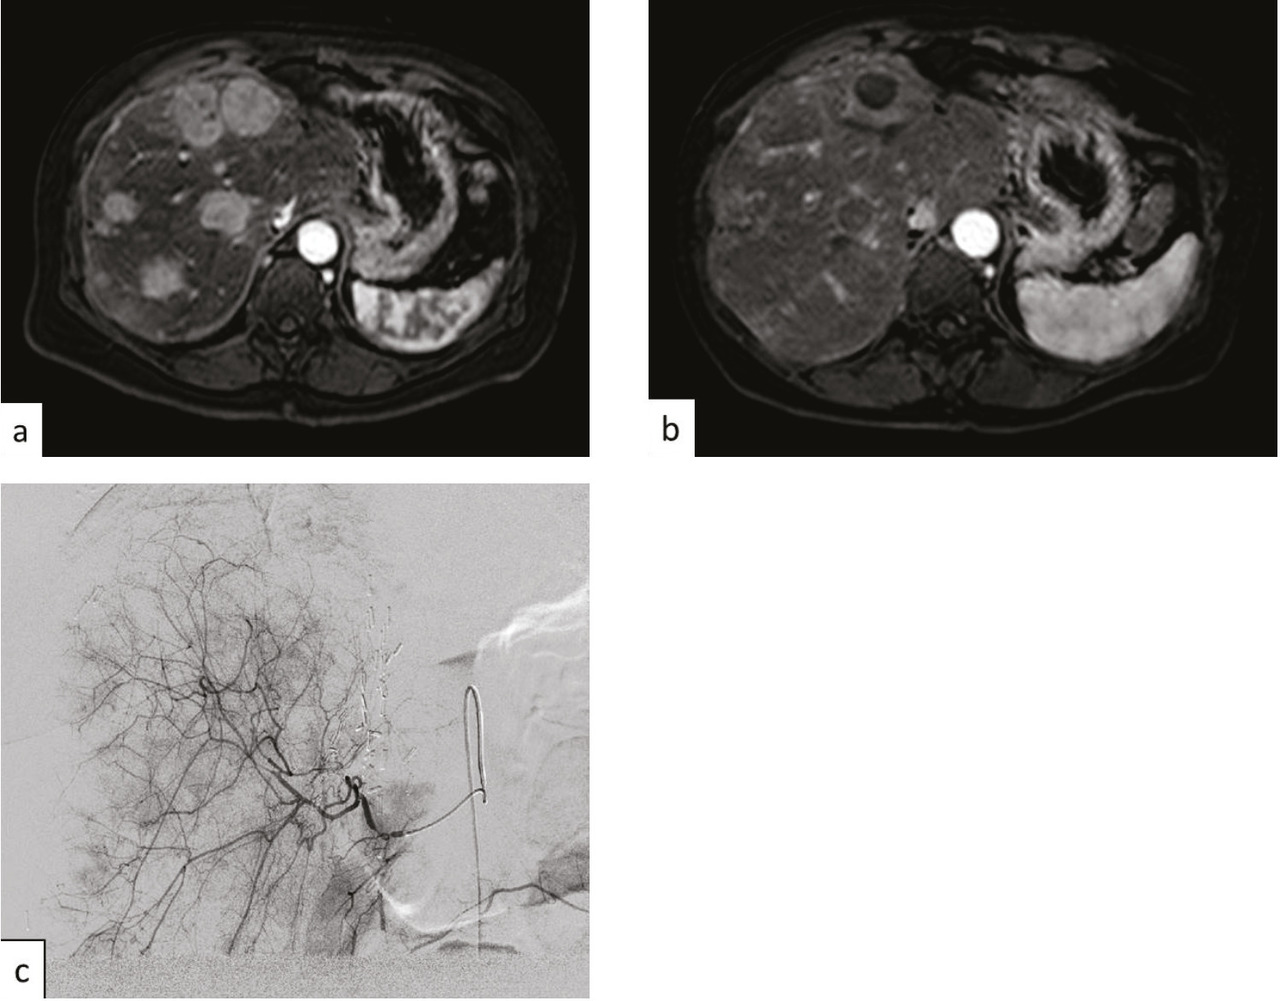

À côté de la voie endovasculaire, une deuxième approche est apparue dans les années 2000 avec l’utilisation d’aiguilles dont l’extrémité est mise en place dans la tumeur par voie percutanée sous contrôle de l’imagerie, le plus souvent l’échographie ou la tomodensitométrie. L’aiguille libère dans la tumeur un courant de radiofréquence qui provoque une augmen- tation locale de la température et la détruit (fig. 6 et 7 ). Ces techniques d’ablathermie constituent un progrès majeur, et d’autres agents physiques tels que les micro-ondes ou la cryogenèse ont été développés par la suite.11, 12 Il est même possible de détruire la tumeur sans effraction cutanée à l’aide d’ultrasons focalisés de haute énergie.13

Les ablations peuvent être thermi- ques par radiofréquences (fig. 6 et 7 ), micro-ondes, laser et cryoablation, on non thermiques par injection d’un agent chimique ou par électroporation.14

Une hépatectomie ne peut être réalisée que s’il reste au moins 30 % de volume hépatique après chirurgie pour éviter une insuffisance hépatocellulaire aiguë postopératoire. Ainsi dans le cas d’un patient qui nécessite une hépatectomie droite en raison de la maladie métastatique et dont le foie gauche est épargné mais a un volume inférieur à 30 %, ce traitement de radiologie inter- ventionnelle guidée par l’imagerie avec embolisation des branches portales droites va permettre d’ob- tenir une hypertrophie hépatique du foie gauche par redistribution vasculaire permettant, dans un délai en général de 40 jours, une intervention chirurgicale. Il est à noter que l’éventuelle présence d’une localisation secondaire dans le foie gauche peut être traitée par thermothérapie dans le même temps que l’embolisation portale (fig. 6 ).